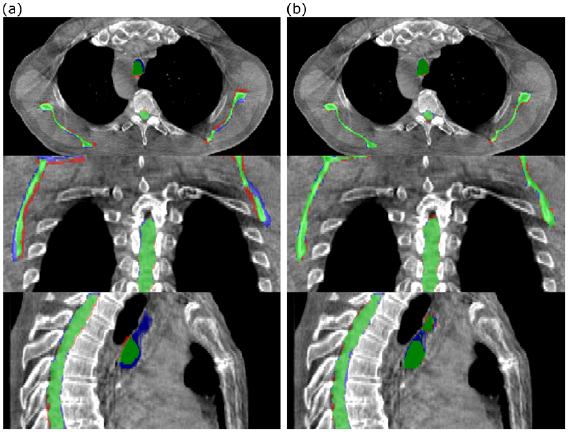

Table 1. Patient summary. Examples of anatomical charge are provided at figure 1.

Figure 1. Examples of minor (Patient 2), moderate (Patient 1) and major (Patient 3) anatomical changes. For each patient the pCT is shown on the left and the CBCT is shown on the right.

Download figure:

Standard image High-resolution imageThe CT images were acquired on a GE Lightspeed Widebore 16 slice CT system (GE Healthcare, Buckinghamshire, UK). For one of the seven patients, the pCT and rCT were helical images and for the remaining six they were 4DCT Average Intensity Projection (AvIP) images. In all cases the pCT and rCT were the images on which dose calculations were originally performed. CBCT images were acquired using the Varian OBI version 1.4 (Varian Medical Systems, Palo Alto) in full rotation half-fan mode with the following parameters; 45 cm FOV, 110 kV, 20 mA and 20 ms. The CBCT acquired immediately prior to the replan was selected for analysis; the time delay between acquisition of the CBCT and rCT varied between zero and five days.

Visual assessment suggested that the structure sets deformed from the pCTs matched well with the gold standard structures directly outlined on the CBCT (figure 5).

Figure 5. Comparison of (a) rigidly aligned and (b) deformed structures with the directly outlined CBCT gold standard for a single patient. Green represents areas covered by both sets of structures, blue represents areas covered by the directly outlined structures only and red represents areas covered by the rigidly aligned/deformed structures only.

Download figure:

Standard image High-resolution imageThe mean results across the seven patient sample for the three volumetrically outlined structures are summarised in table 2.

The deformed structures performed consistently better than the rigidly aligned structures for each of the metrics measured. For every structure, a DSC of 0.88 or greater was achieved by the deformable registration. The results for the spinal canal were better than for the other structures, which is unsurprising given the relative rigidity of the structure, its insensitivity to setup differences and its clarity on CBCT images. The trachea produced the most variable results across patients, as evidenced by the relatively high standard deviations for each of the metrics. This soft tissue structure underwent the most anatomical change across the patient dataset and so presented the greatest challenge for the registrations. The scapulae Could you use plural scapulae throughout to be consistent produced well-matched results across the patients for deformed structures which were comparable to those for the spinal canal. During our preliminary DIR parameter optimisation work we found the scapulae, on visual appraisal, to be particularly sensitive to registration errors. This was also found in a previous study by Veiga et al (2016).